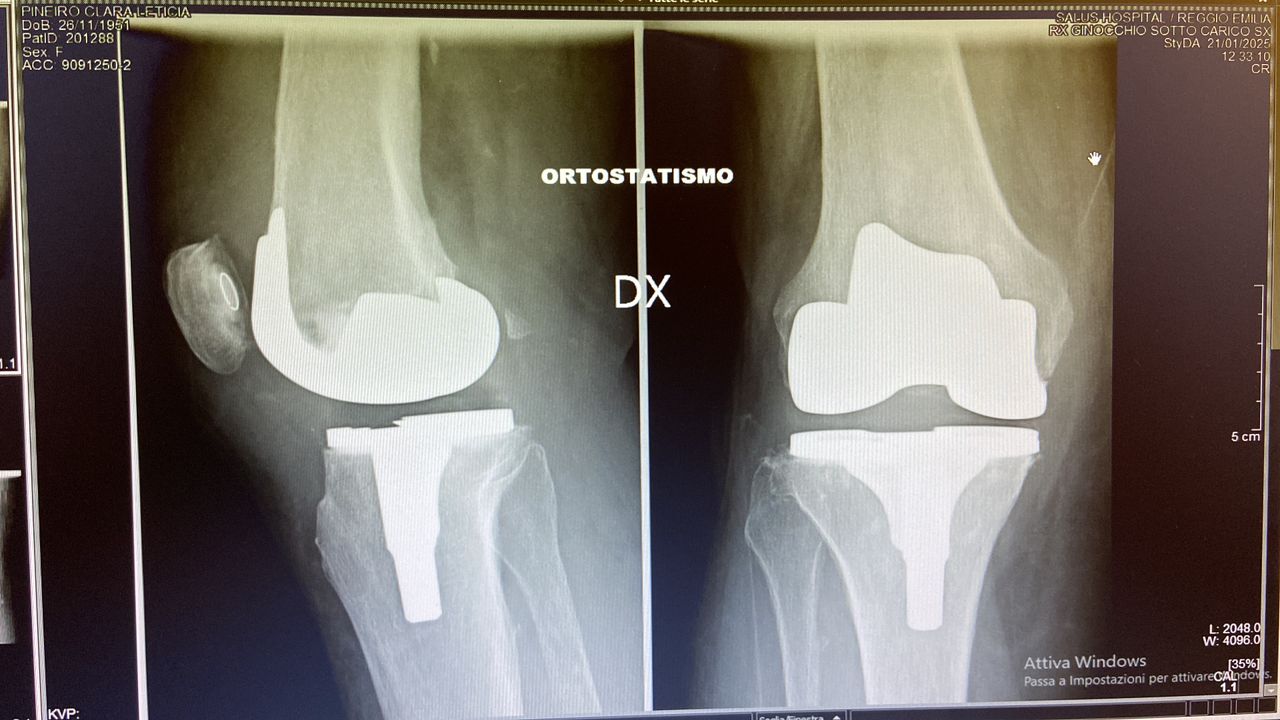

Foto e video